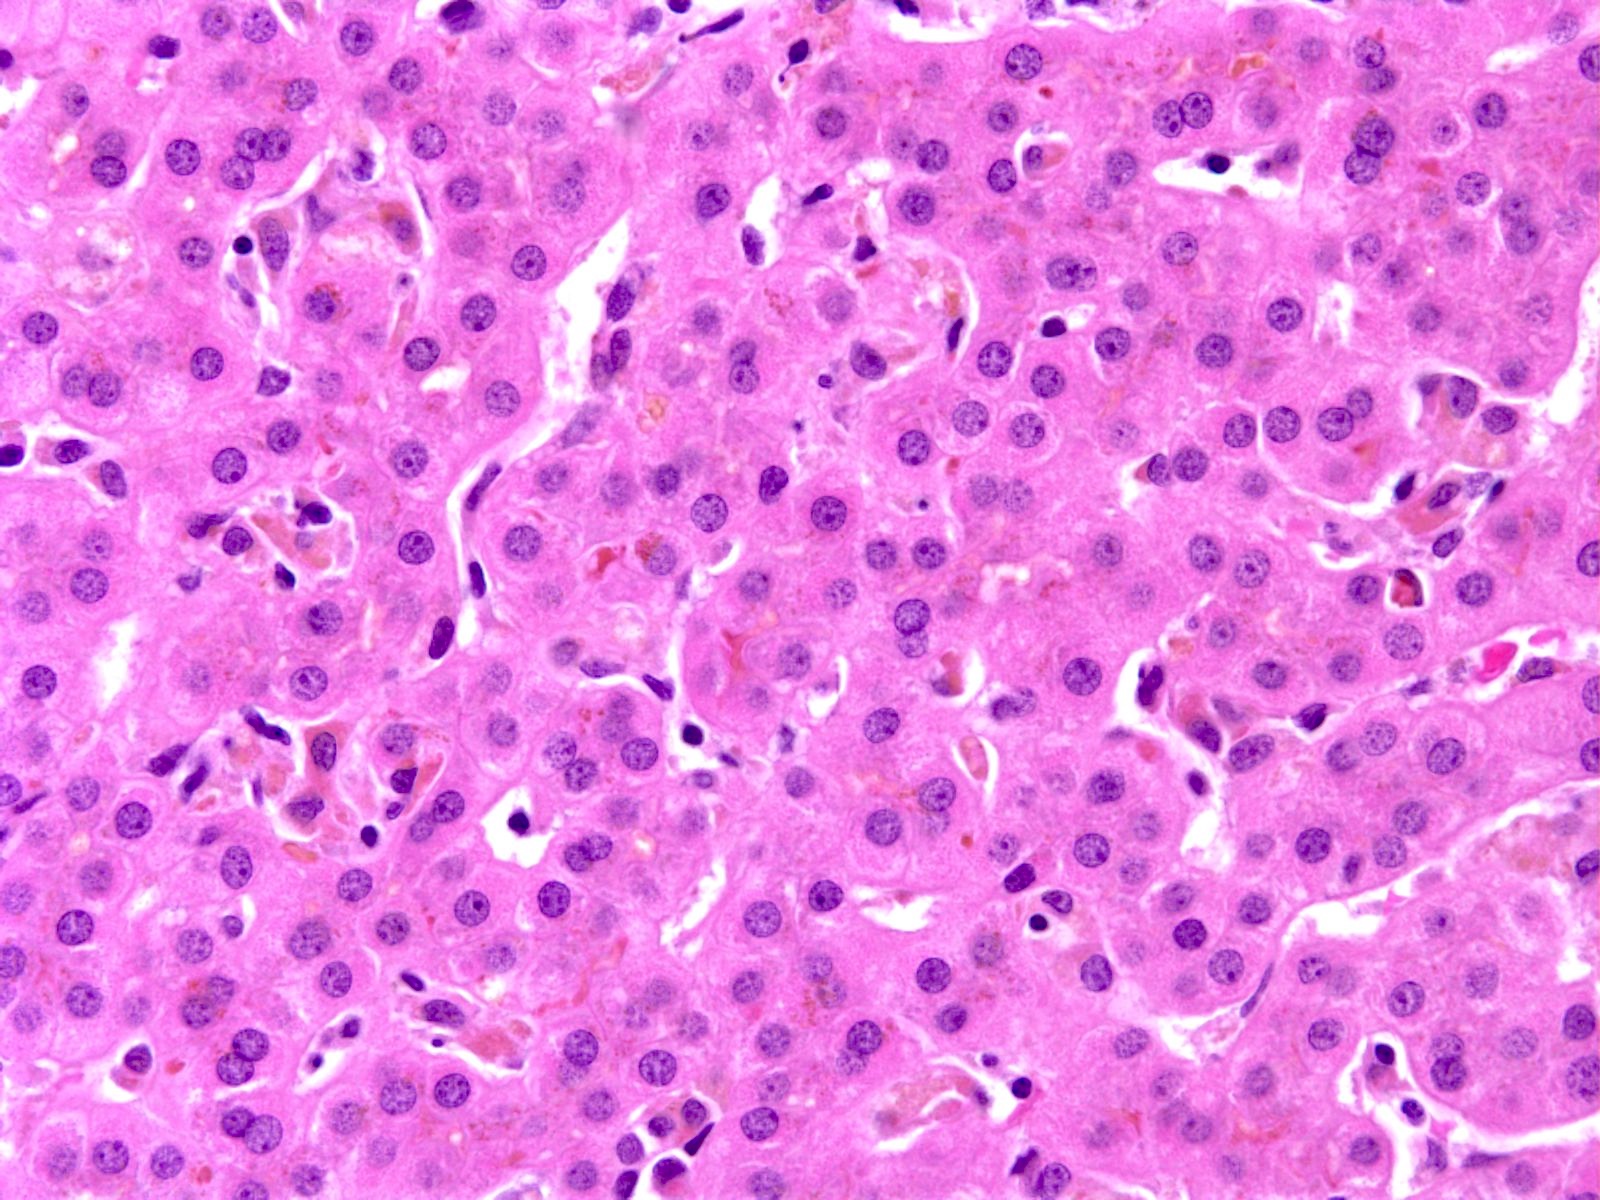

Microscopic (histologic) description

- Canalicular and intracellular cholestasis with associated hepatocyte rosettes

- No associated inflammation, bile duct loss or marked ductular reaction

- No advanced fibrosis

- Reference: Case Rep Gastrointest Med 2020;2020:2894293

Microscopic (histologic) images

Sample pathology report

- Liver, biopsy:

- Liver parenchyma with mild cholestasis (canalicular and intracellular); no fibrosis (see comment)

- Comment: The patient's history of recurrent attacks of jaundice and pruritis are noted. Sections show liver core biopsies with bland cholestasis (both canalicular and intracytoplasmic). No associated inflammation, bile ductular reaction or bile duct loss is seen. No fibrosis is seen.